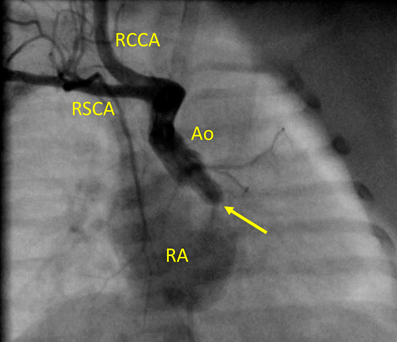

Fig. 1 Fetal echocardiography at 29 weeks of gestation reveals hypoplastic left heart syndrome. Color Doppler image suggests moderate tricuspid regurgitation (arrow)

See Movie A. LV, left ventricle; RA, right atrium; RV, right ventricle

日齢0の女児.母体19歳,1経妊0経産.自然妊娠で妊娠成立した.胎児心奇形が疑われ,在胎29週5日に当院を受診した.胎児心エコー検査では,僧帽弁と大動脈弁は閉鎖し,上行大動脈の血流は動脈管を介して逆行性に維持されていた.心室中隔欠損を合併していたが左室は痕跡的であり,心室中隔欠損を合併した非典型的な左心低形成症候群と診断した.右房に吹き込む血流を認め,三尖弁逆流と診断した(Fig. 1, Movie A).右室の収縮は良好であった.在胎37週5日の再検査でも同様の所見で,心拡大や心不全の進行はみられなかった.在胎38週2日に選択的帝王切開で出生し,アプガースコアは1分値7, 5分値8であった.左心低形成症候群に対する全身管理目的でPICUに入院した.